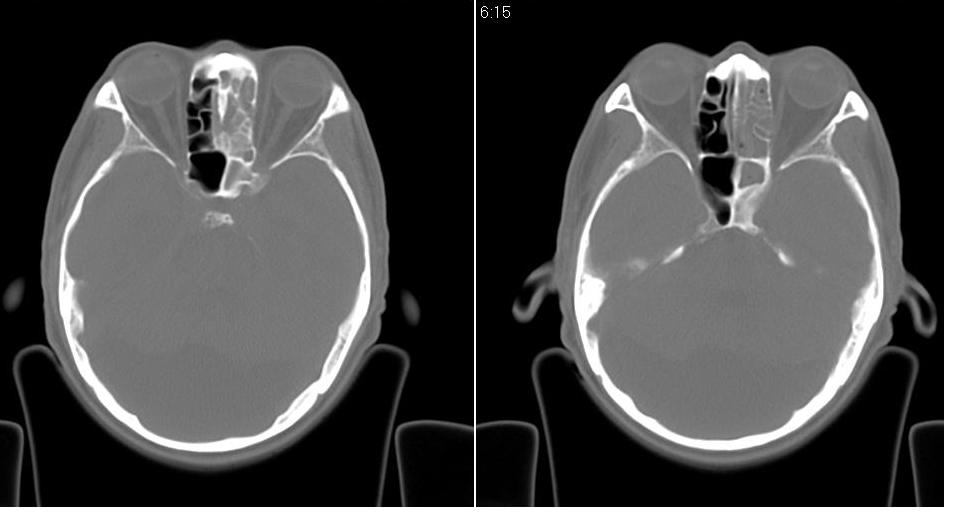

以下是引用zrs在2009-4-21 18:22:00的发言:[br]左侧额窦、筛窦及上颌窦内均充以软组织密度影,且窦壁骨质明显增厚,右侧上颌窦粘膜环形增厚。左侧鼻腔内亦见软组织密度影。考虑慢性鼻窦炎。

以下是引用hnfsh在2009-4-21 19:56:00的发言:[br]病灶主体位于左侧鼻腔内,呈膨胀性生长,鼻中隔、左侧筛板骨质吸收破坏,双侧上颌窦、额窦内聪充满软组织密度影。 考虑:1。左侧鼻息肉 2。慢支副鼻窦炎

以下是引用张xyz在2009-4-21 20:59:00的发言:[br]全组副鼻窦炎并息肉样变[br]